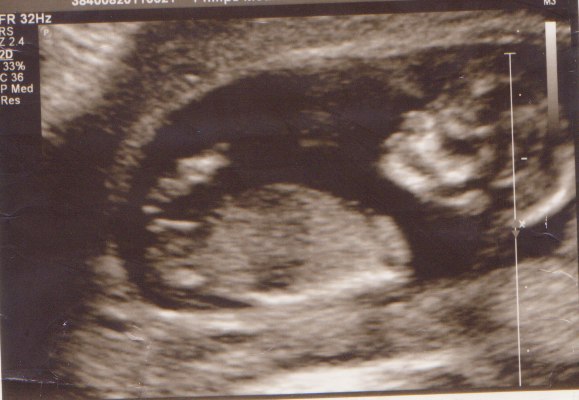

Vedhæfter lige billedet, hun gættede ud fra, så du kan komme med dit gæt - er super spændt på at se, om I er enige

Vedhæftede fotos (klik for at se i fuld størrelse)